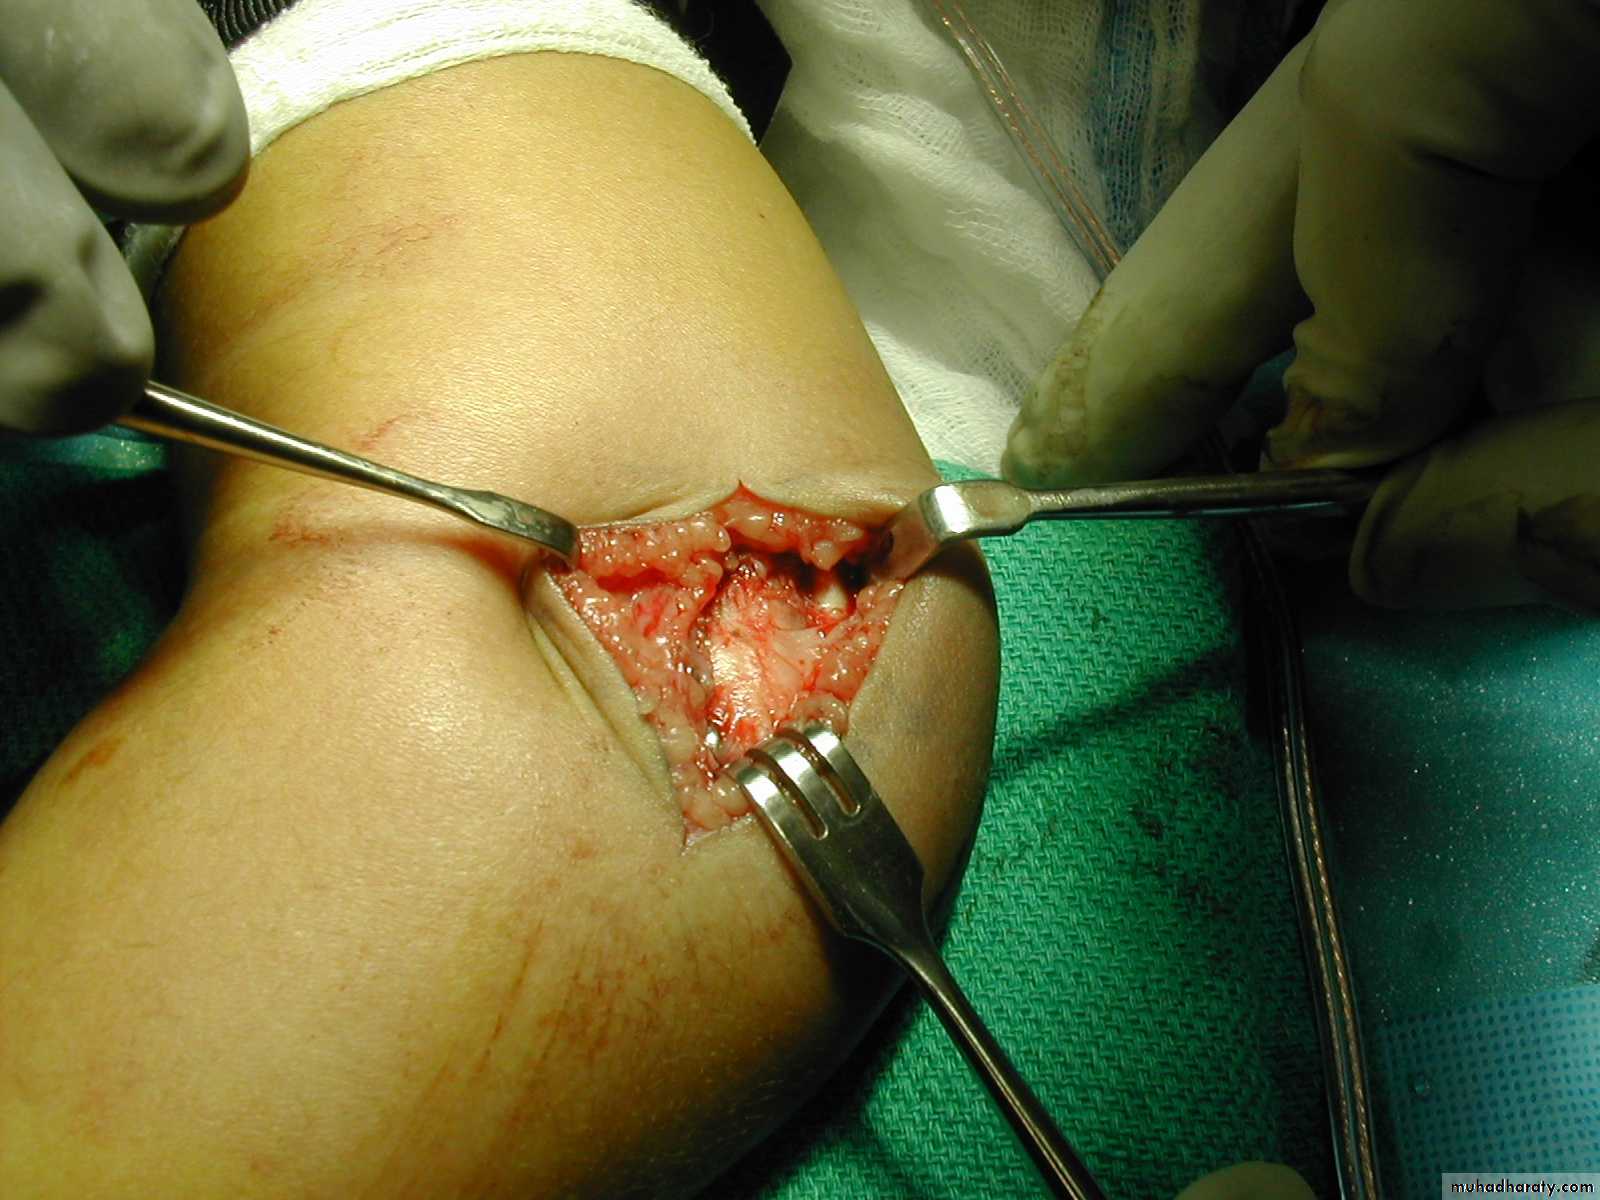

injury be minimized?By

making an incision

directly over the

medial epicondyle,

to locate the

medial epicondyleby direct vision.

Then, insert the medial pin by direct vision

into the center of the medial epicondyle.while the ulnar nerve

is

retracted posteriorly.